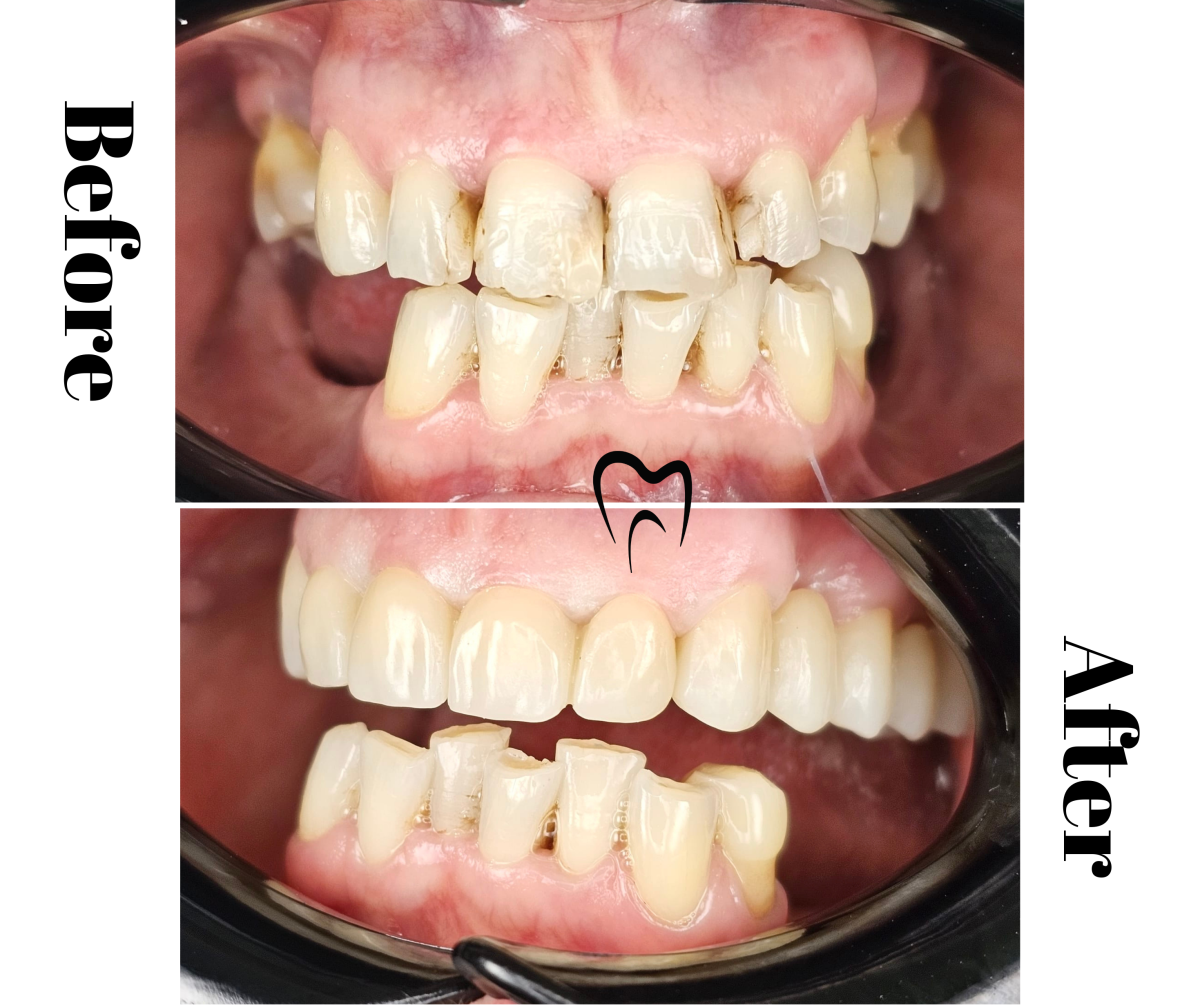

Restaurare frontală cu coronițe de zirconiu

Detalii caz